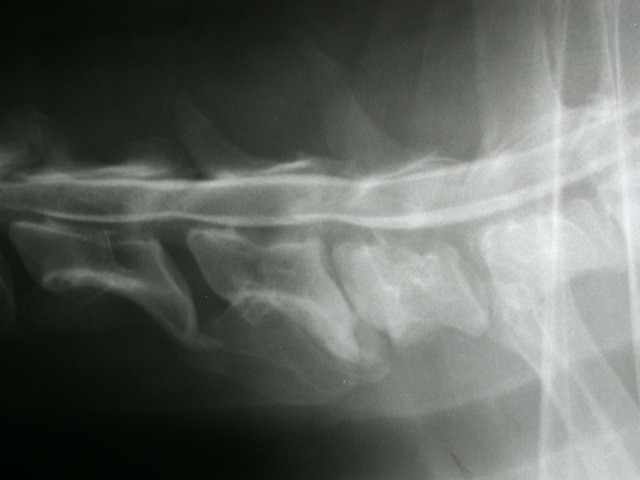

Instabilität der Halswirbelsäule bei einem Dobermann

(Wobbler-Syndrom)